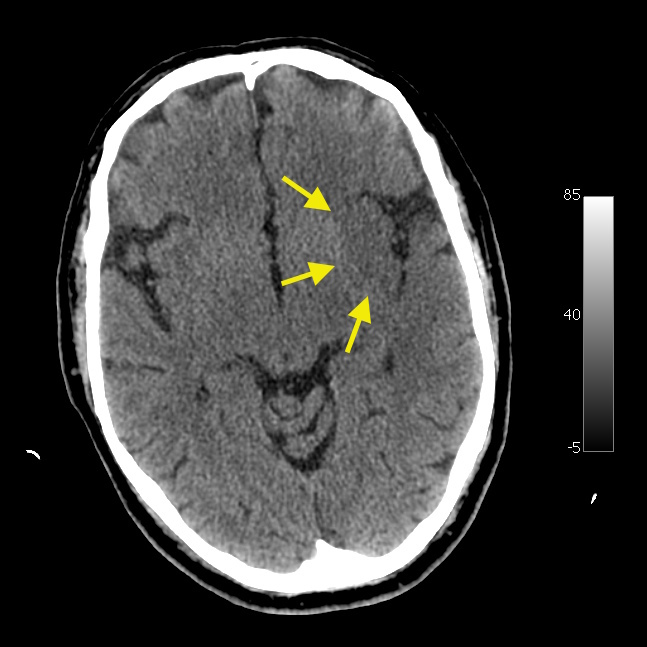

豆状核模糊

正常状态下,通过 CT 能够清晰观察到三角形状的豆状核,以及其内侧的内囊膝部、前后支,外侧低密度的外囊和岛叶皮层。然而,一旦发生脑梗死,豆状核边缘会变得模糊,内外囊与豆状核的分界不再清晰,岛叶皮层也可能出现肿胀的低密度影。